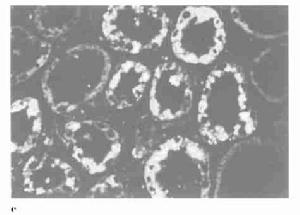

(1)光鏡:

Ⅰ型膜增殖性腎小球腎炎主要改變是瀰漫性的毛細血管壁增厚和血管內細胞增生,還有單個核白細胞和中性粒細胞浸潤。系膜區和毛細血管壁由於細胞增生和基質增加而呈現不同程度的擴張,通常是均一地影響幾乎所有的小葉,可引起毛細血管叢的分葉結構突出,因此早期稱這一病變為小葉性腎小球腎炎。至於分葉型和非分葉型病變之間是否存在因果或先後關係,至今尚無定論。系膜區明顯擴張形成結節狀,結節中間區可有硬化灶,與糖尿病腎小球硬化或者輕鏈沉積病的病變相似,但是結合光鏡、免疫螢光和電鏡的結果就可以容易地將本病和其他疾病區分開來。另一明顯但不是特異的表現是腎小球基底膜增厚,用適當的染色(如銀染或過碘酸希夫酸染色)可以很容易看到呈雙軌狀或者多層,這是由於增生了的系膜細胞及其基質伸展和插入基膜與內皮細胞之間,形成間位所致,即插入的系膜形成偽基底膜,而不是一般認為的基底膜分裂。偶爾可在內皮下部位見有嗜伊紅沉積物。少數患者可有新月體,但很少累及50%以上的腎小球,與其他的腎炎一樣,如有大量新月體則提示預後不良。晚期病人常有間質纖維化、小管萎縮和間質單核炎症細胞浸潤。毛細血管腔內出現“透明血栓”,提示病變可能繼發於冷球蛋白血症或者系統性紅斑狼瘡。“透明血栓”並不是真正的血栓,而是免疫複合物充填毛細血管腔所致。腎活檢光鏡下可將MPGN分為5個亞型:①分葉型:毛細血管襻呈明顯的分葉狀,主要以細胞增生為主,也可以伴有不同程度的硬化。②經典型(雙軌型):由於系膜插入而使基底膜瀰漫性增厚,出現雙軌,分葉狀不典型。③混合型:系膜插入和分葉狀雖不典型,但是在基底膜的上皮下、內皮下及系膜區內都有免疫複合物沉積,系膜細胞增生及基質增生,基底膜明顯肥厚。這種類型與狼瘡性腎炎的瀰漫增生型非常相似,有人稱之為混合性膜性和增生性腎小球腎炎。④局灶型:MPGN的改變只占全部腎小球的50%以下。⑤新月體型:50%以上的腎小球出現新月體。